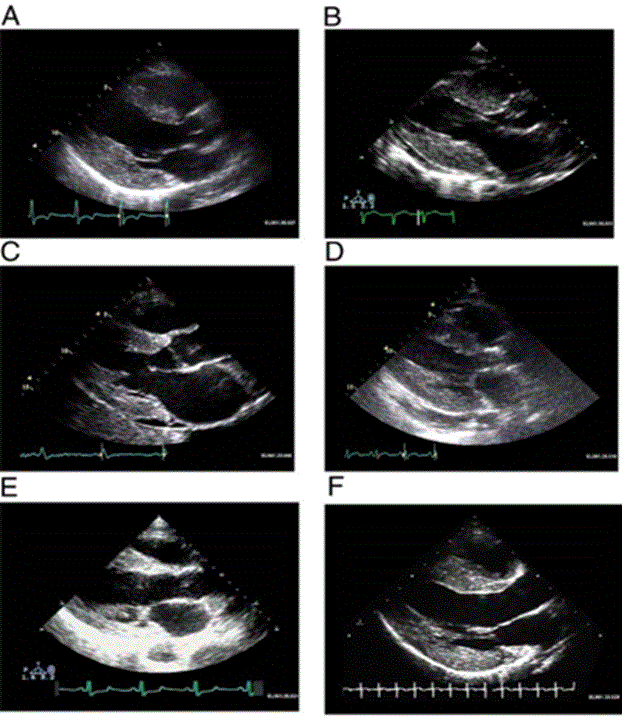

Cardiac amyloid characteristic echocardiographic appearance involves increased thickening of the LV and right ventricular walls, normal LV cavity size, as well as a nonspecific granular appearance of the myocardium, as shown in Figure 2. The cardiac amyloid is also characterized by atrial enlargement, thickened papillary muscles, small to moderate pericardial effusion, as well as valve leaflets [2].

Figure 2: Increased LV Mass and Thickening of Ventricular Walls in Cardiac Amyloidosis

(A) Hypertrophic non-obstructive cardiomyopathy; (B) Hypertensive heart disease with secondary renal failure; (C) Cardiac amyloid; (D) Mucopolysaccharidosis; (E) Cardiac oxalosis; (F) Friedreich ataxia. Adopted From: Seward and Casaclang-Verzosa, (2010), p.1774, [2]